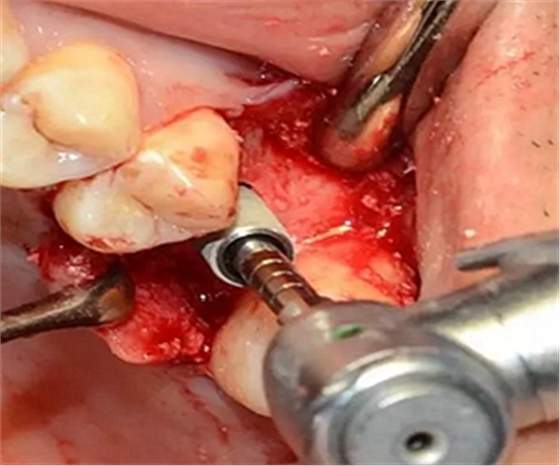

植入種植體,注意方向控制和初期穩(wěn)定性。

上覆蓋螺絲